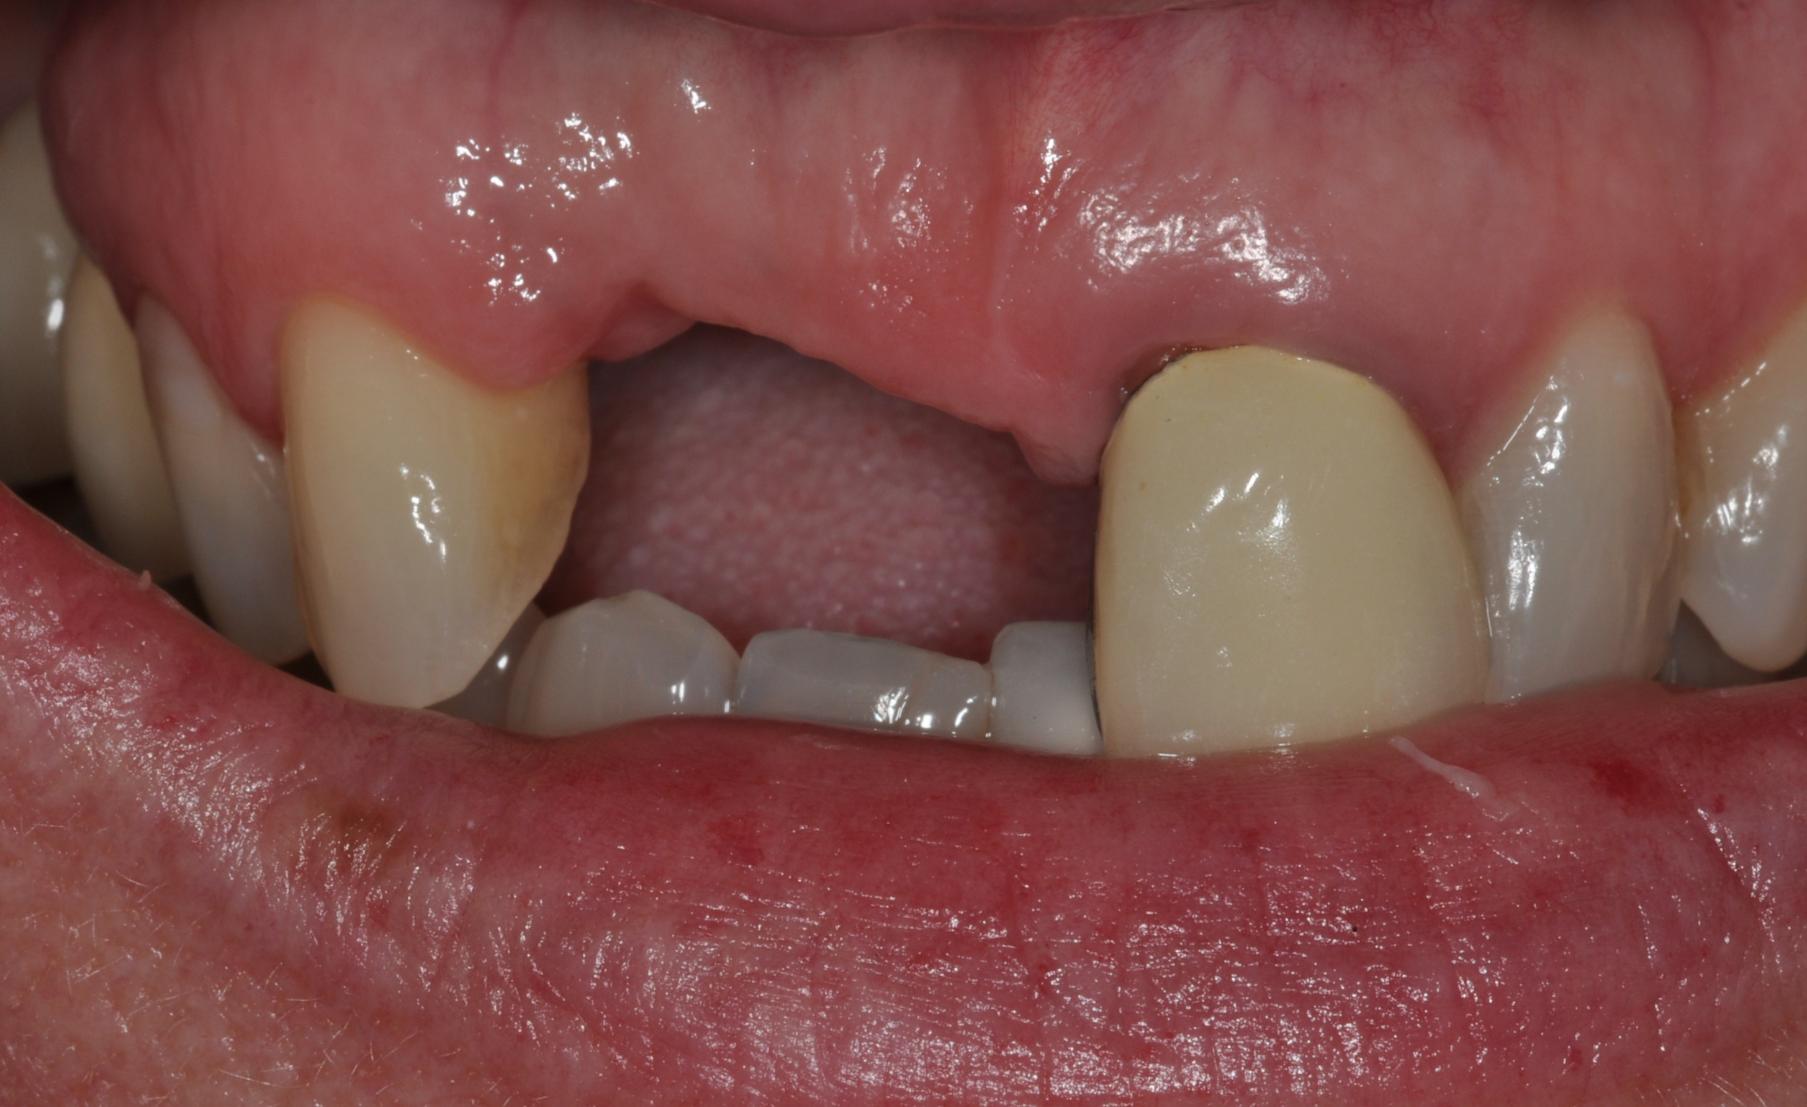

Dental Implant Treatment

Before After

Before Image

After Image